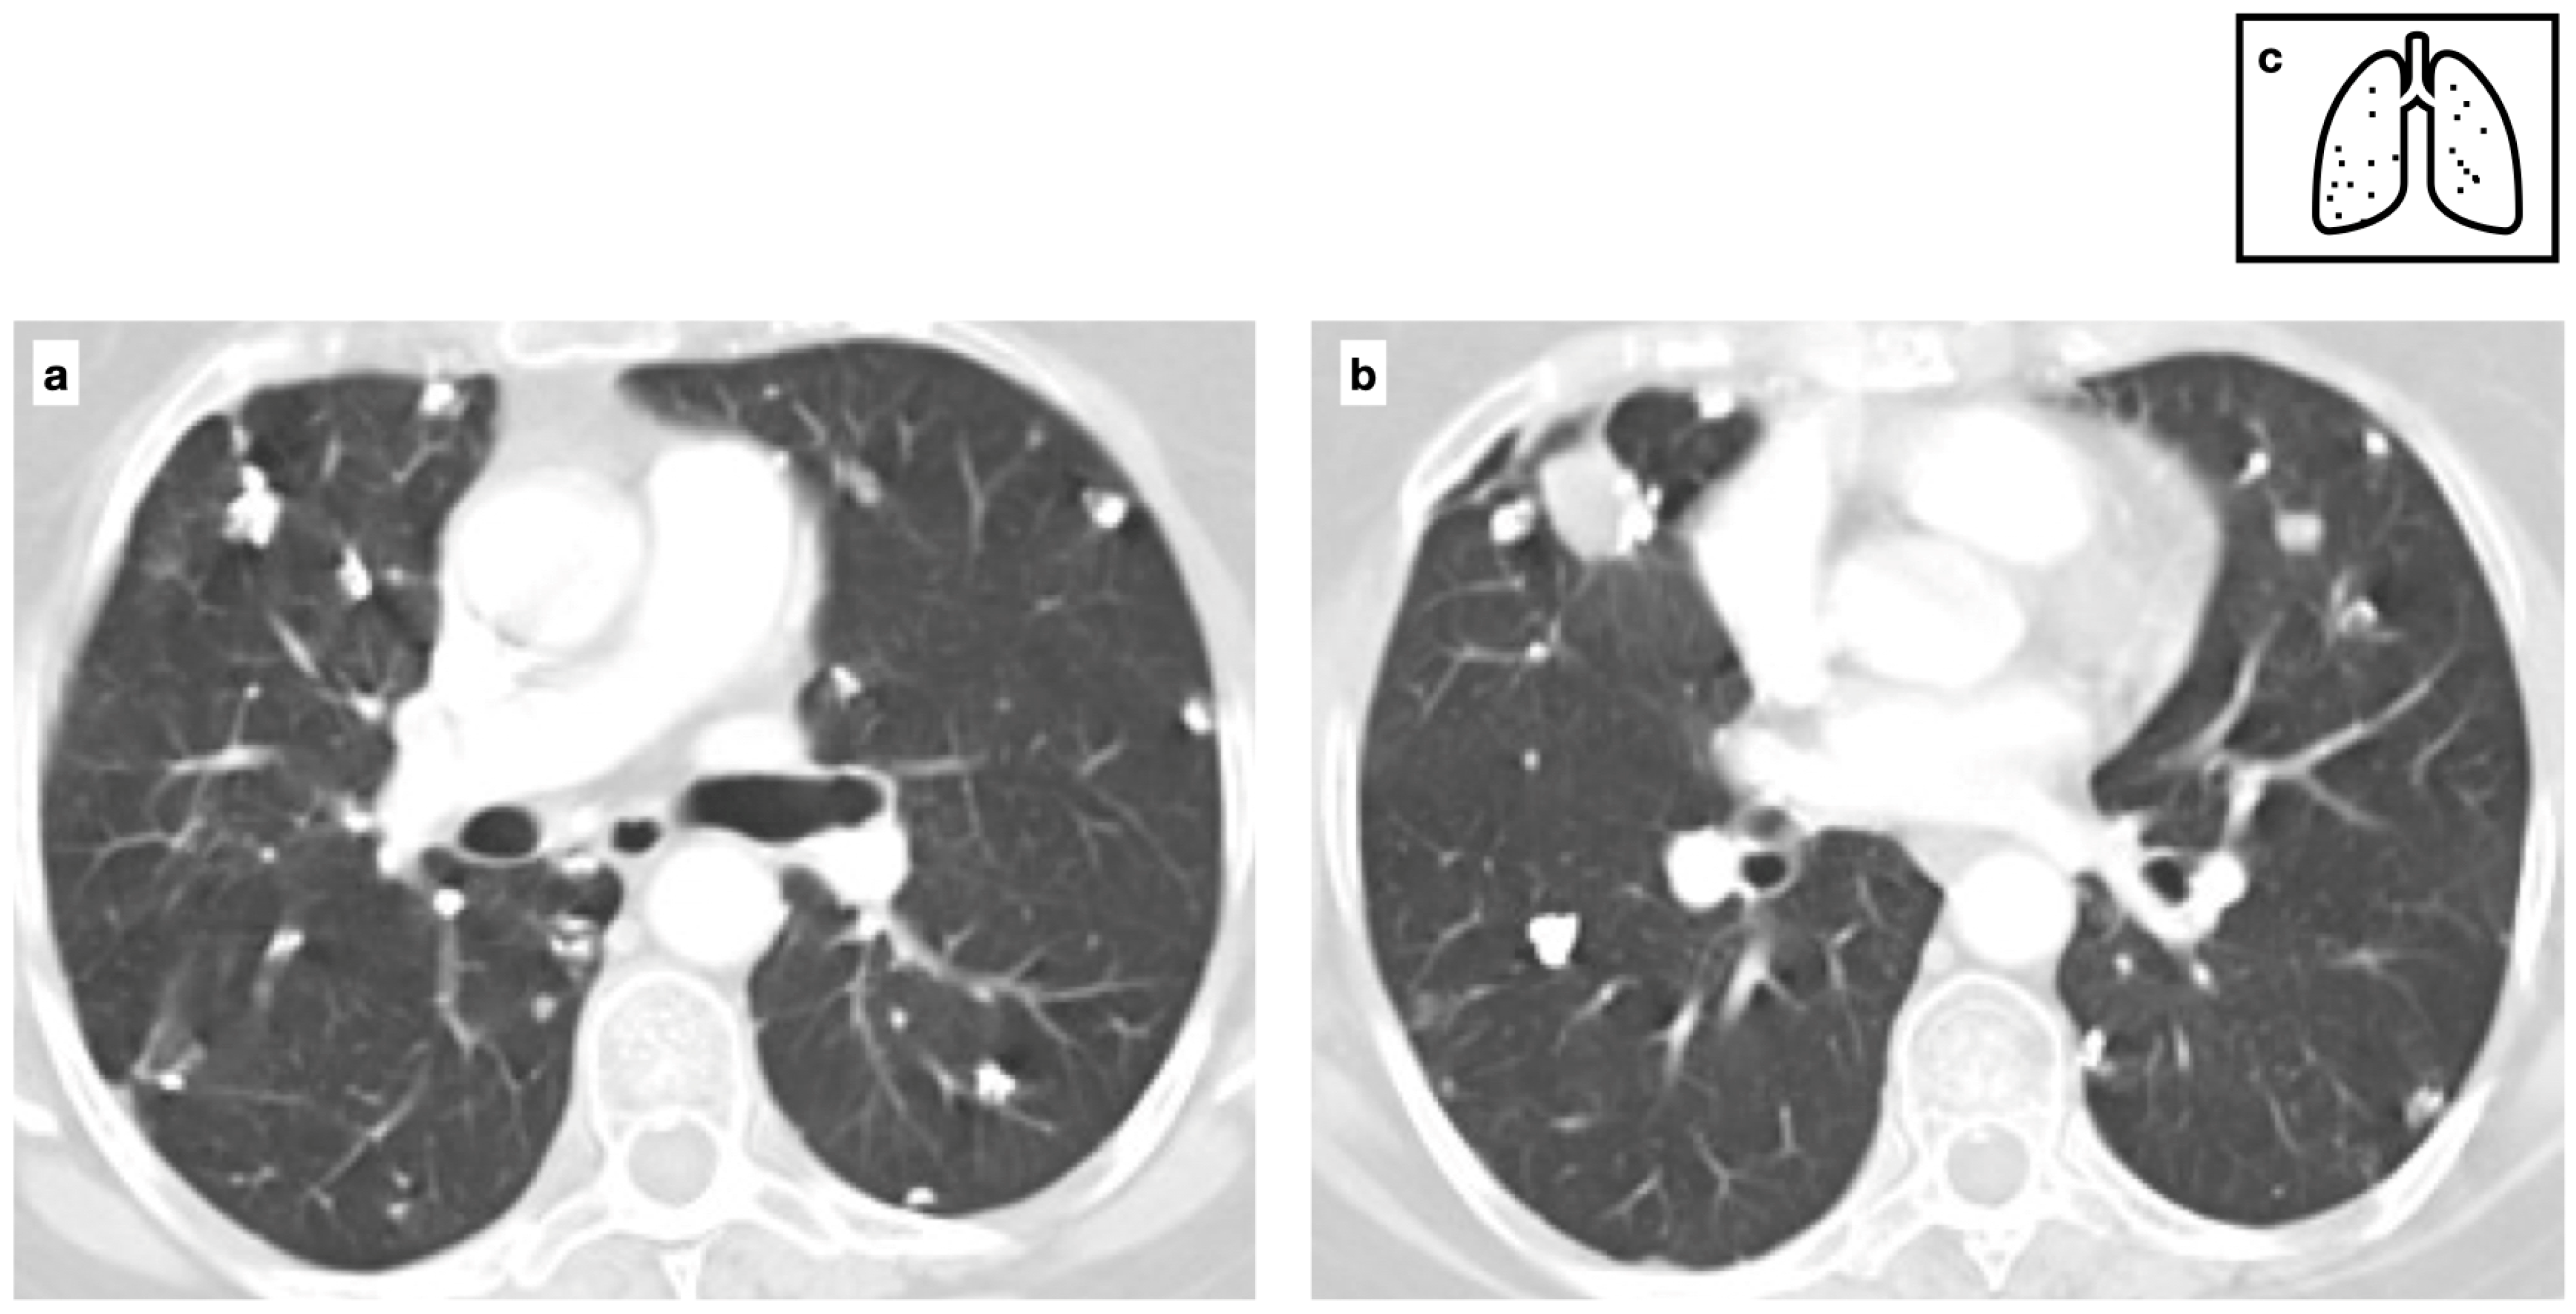

Figure 5.

Patient with previous history of severe varicella pneumonia. HRCT shows bilateral diffuse ill-defined calcified nodules. Scattered diffuse micronodular calcifications are an uncommon late sequela of VZV pneumonia (a,b). Pattern of calcification (c).

In patients with a history of severe VZV pneumonia, scattered diffuse micronodular lung calcifications are an uncommon late sequela (Figure 5). In these cases, mediastinal lymph nodes are usually not calcified [13,14].